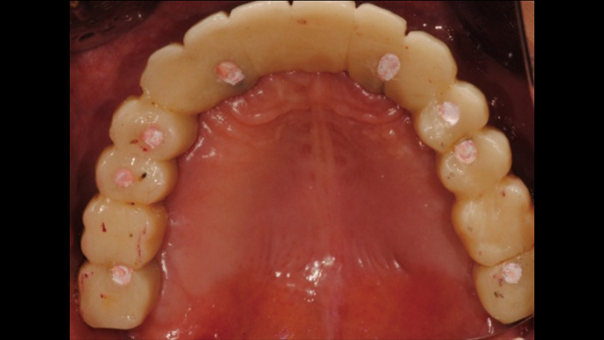

Clinical case: AFull transition from natural teeth to all-on-6 bridges

with AnyRidge implants

- Courtesy of Dr. Rabih Abi Nader, UAE -